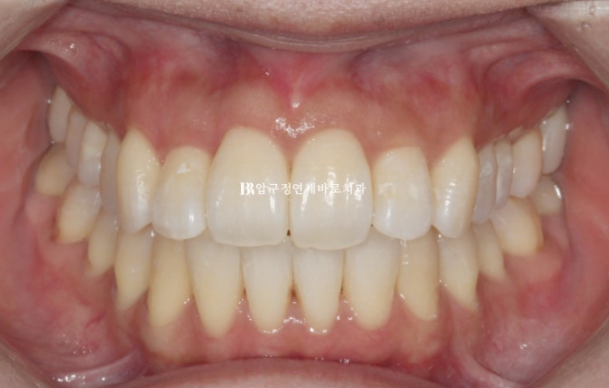

2달 간 마무리 교정 후 치료시작 6개월 만에 치료를 마무리 했습니다.

24.08

정확히 맞아 떨어지는 중심선

마치 전체교정 한 것과 같은 효과를 목표로 치료에 임합니다.

앞니 부분교정은 치료기간도 짧고 간단해보이지만 전체교정을 한 것과 같은 효과를 얻기는 쉽지 않습니다.

내려와 토끼이처럼 보이던 앞니는 높이가 맞아졌고 기울어짐도 치축개선을 통해 좋아졌습니다.

걸려있던 앞니도 제 위치를 찾았습니다.